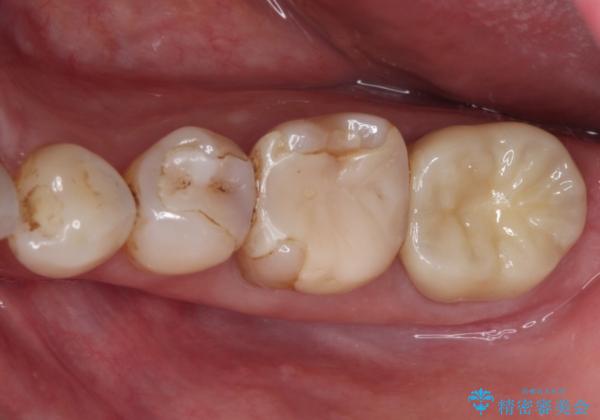

仮歯を装着した時点でものが挟まる症状は改善されました。

根管治療により咬合時の違和感も解消されました。